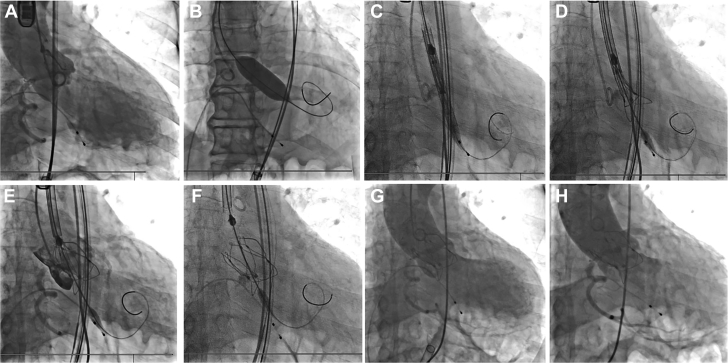

Figure 3.

Procedure

(A) Live fluoroscopy illustrating the root of aorta. (B) The balloon inflation at the calcified aortic valve. (C) Passing the delivery system. (D) Gradually deploying the valve after aligning the reference points with orthotopic annulus. (E) Confirming valve position and coronary blood flow. (F) Completing valve deployment. (G) Immediate angiography showed moderate perivalvular leakage. (H) The perivalvular leakage decreased to mild after 15 minutes.

Management

TAVR was performed under general anesthesia. The right femoral artery of the patient was chosen, as the primary vascular access with a 22-F-long introducer. The stenotic aortic valve was dilated using a balloon catheter with a diameter of 20 mm and a length of 40 mm. A 26-mm polymeric valve was advanced through a 22-F sheath. After passing through the aortic arch, the cusp overlap and commissural alignment were achieved. The delivery system was then moved to a predetermined height; the annulus marker was located 2 mm above the sinus plane to yield the largest radial support force based on preoperative CT analysis and annulus simulation. The valve was released during pacing at 180 beats/min (Video 3). Transesophageal echocardiography and digital subtraction angiography showed the valve in the correct position but moderate PVL (Figure 3, Video 4). After 15 minutes, the PVL improved to mild severity (Figure 3, Video 5). The average transvalvular pressure was 4 mm Hg and the effective orifice area (EOA) was 2.3 cm2. No new conduction blocks were observed. His symptoms gradually improved within 48 hours. The PVL remained mild and the EOA increased to 2.8 cm2. The patient was discharged on the sixth day postoperation.